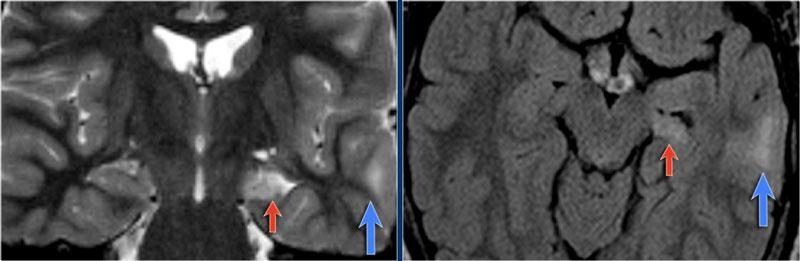

Hình ảnh của bệnh nhân nam 27 tuổi bị động kinh thùy chẩm kháng trị.

Ảnh FLAIR mặt phẳng coronal và T2W mặt phẳng axial cho thấy dày vỏ não tăng tín hiệu T2 và tăng tín hiệu ở vỏ não và vùng dưới vỏ.

Lưu ý vùng tăng tín hiệu dưới vỏ kéo dài đến não thất bên phải, biểu hiện dấu hiệu xuyên vỏ (mũi tên xanh).

Dấu hiệu xuyên vỏ (transmantle sign) ghi nhận ở một bệnh nhân khác bị loạn sản vỏ não khu trú.